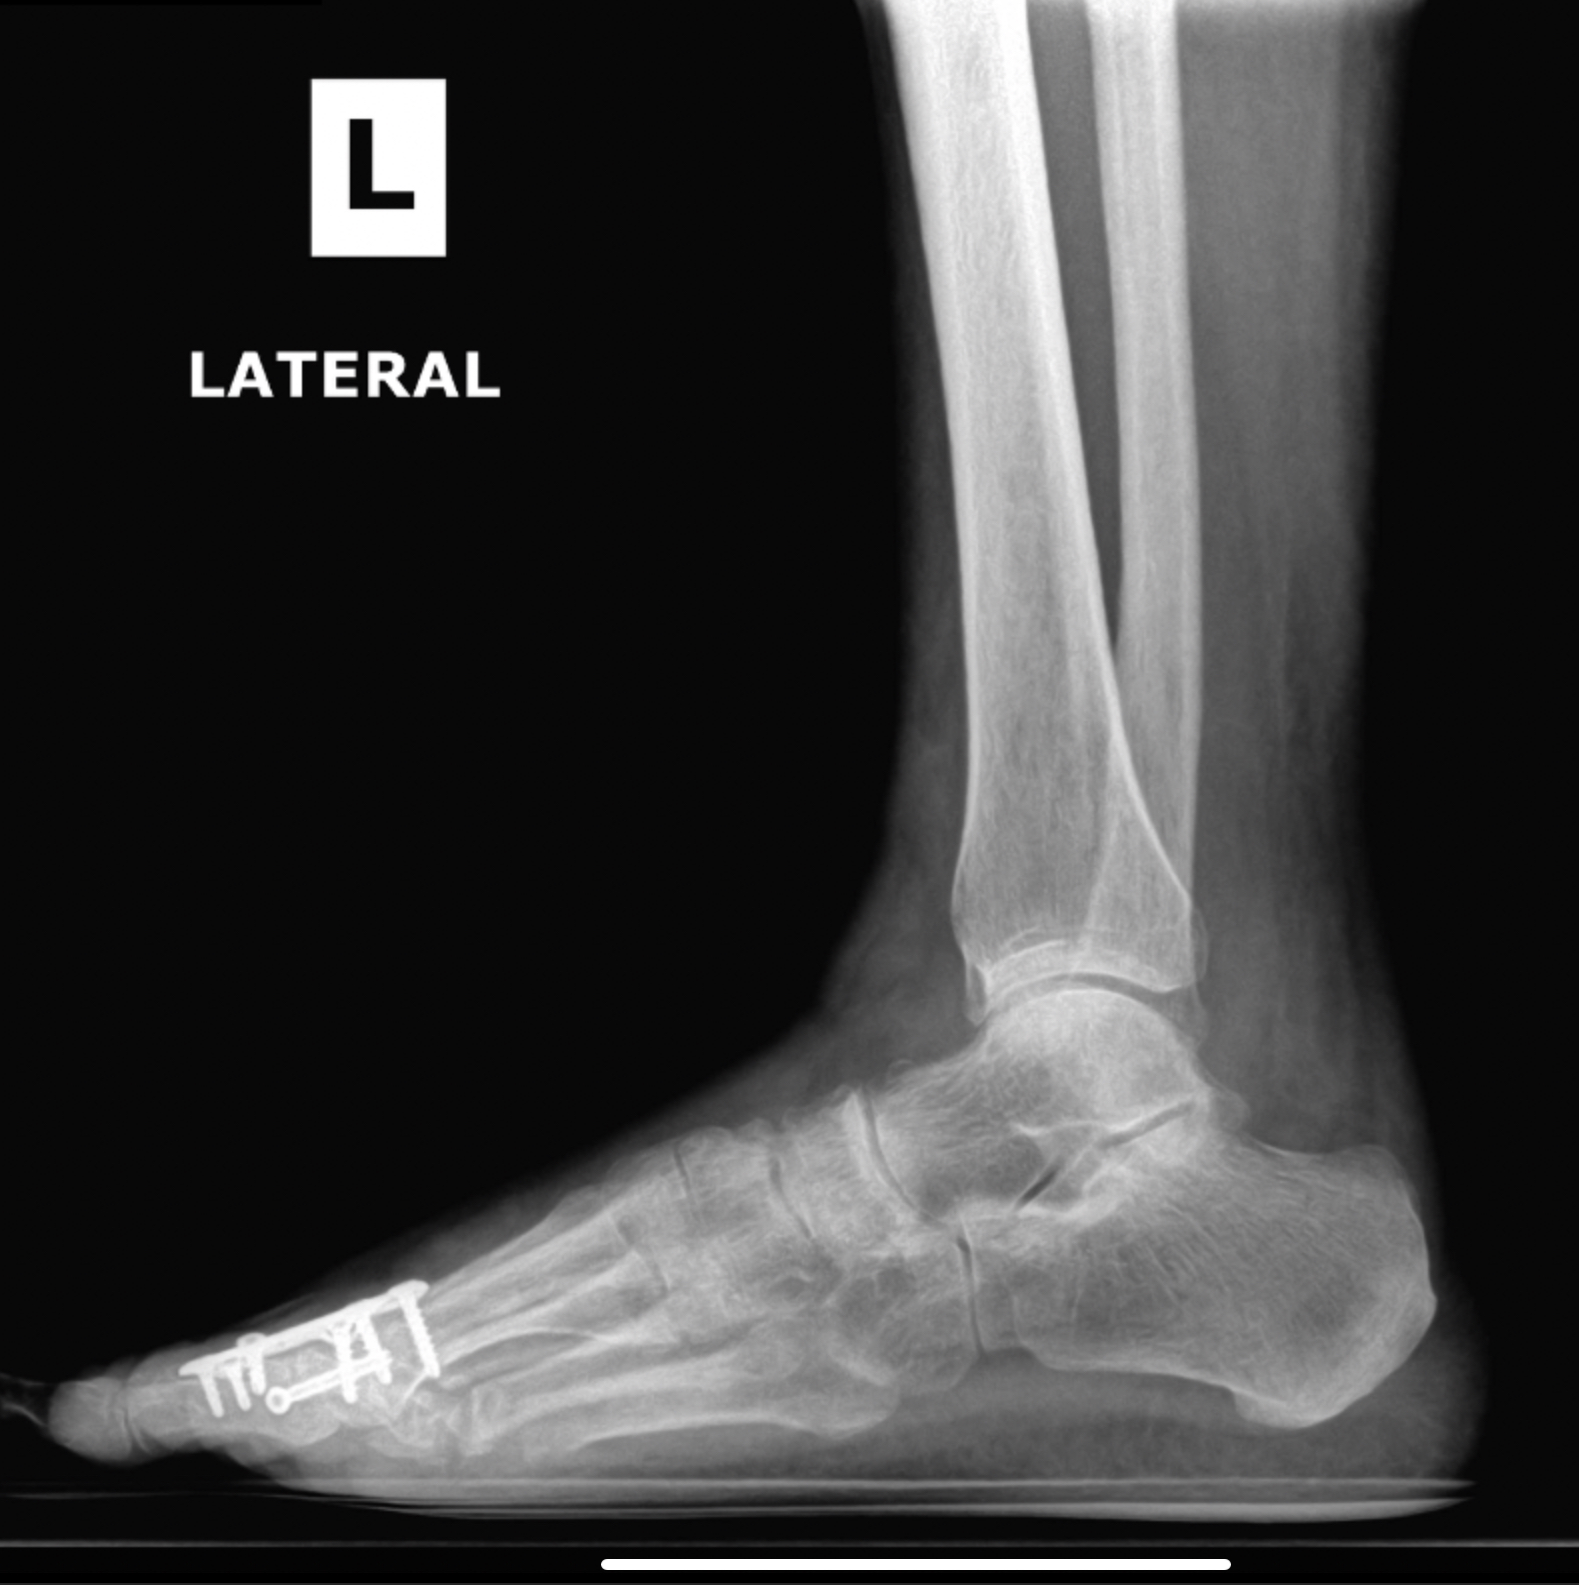

Flatfoot deformity

Patient 1

Patient 2